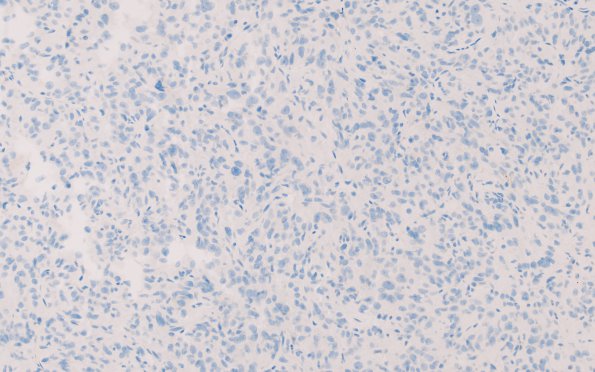

Tumor cells are not GFAP immunoreactive. (GFAP IHC) ---- Not shown: Tumor cells are negative for HMB-45, synaptophysin, EMA, and CAM 5.2. Ki-67 (MIB-1 antibody) shows a proliferation index up to 4.4%. A compressed normal adenohypophysis is highlighted by synaptophysin and CAM 5.2. Periodic acid Schiff (PAS) does not strongly stain the cytoplasm of tumor cells. ---- Taken together, these findings are most consistent with a diagnosis of TTF-1-positive sellar tumor. Tumors of the posterior pituitary comprise three diagnostic entities (pituicytoma, spindle cell oncocytoma, and granular cell tumor of the sellar region) which share a common molecular signature: TTF-1 immunoreactivity. Given this fact, it has been suggested that these three entities represent a morphological spectrum of a single nosological entity